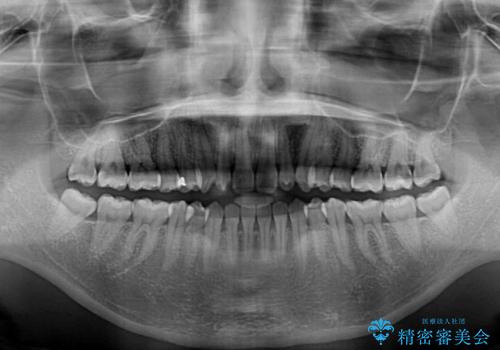

- 上顎前歯の叢生を気にして来院された患者様です。

下顎前歯や上下奥歯の咬み合わせには殆ど問題がないため、上顎前歯のみを矯正する治療を提案しました。

ワイヤー装置でもインビザラインでも可能でしたが、前歯のみをきれいに排列するのであればインビザラインの方が仕上がりが良いので、インビザライン・ライトにて治療を行うこととしました。